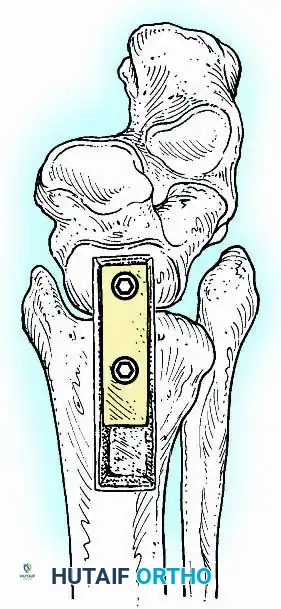

Knee Arthrodesis

While total knee arthroplasty (TKA) is the definitive treatment for knee osteoarthritis, knee arthrodesis remains a critical salvage procedure. The primary indications are a chronically infected TKA that has failed two-stage revision, massive extensor mechanism disruption, severe neuropathic arthropathy, and tumor resection.

Positioning and Technique

The optimal position for knee arthrodesis is 10 to 15 degrees of flexion and 5 to 7 degrees of valgus. This slight flexion assists in foot clearance during the swing phase of gait and makes sitting in confined spaces more manageable. A perfectly straight (0 degrees) knee is cosmetically awkward and functionally detrimental, causing a vaulting gait pattern.